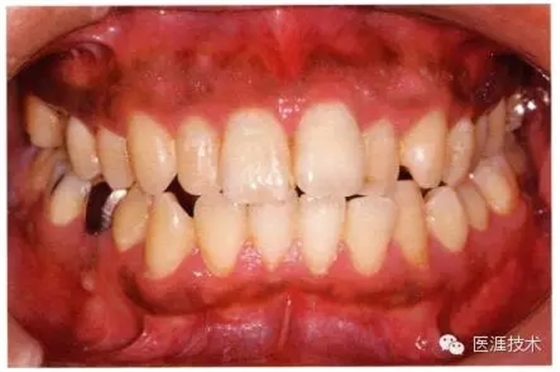

44歲牙周炎女性的臨床照片

44歲患有糖尿病病史(未治愈)。菌斑控制不良。通過牙周探診,全頜有4~8mm的牙周袋,在X光片中可以看到上頜前牙處中度牙槽骨吸收,磨牙處重度牙槽骨吸收。二次齲齒和根面齲齒也有發(fā)生。可以看到浮腫性腫脹,收到刺激后會出血。